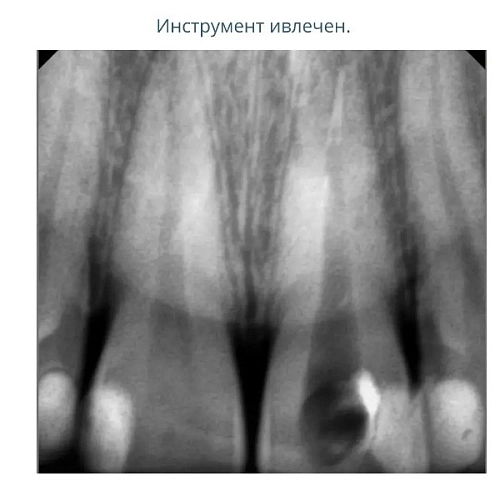

На фото представлен клинический случай.

Пациент обратился в нашу клинику с жалобой на боль при надкусывании .

При проведении первичной диагностики доктор выявил наличие сломанного инструмента в корневом канале, который привёл к воспалению.

На следующем снимке - отломок сломанного инструмента извлечён. Все каналы пройдены, механически обработаны под микроскопом и запломбированы.